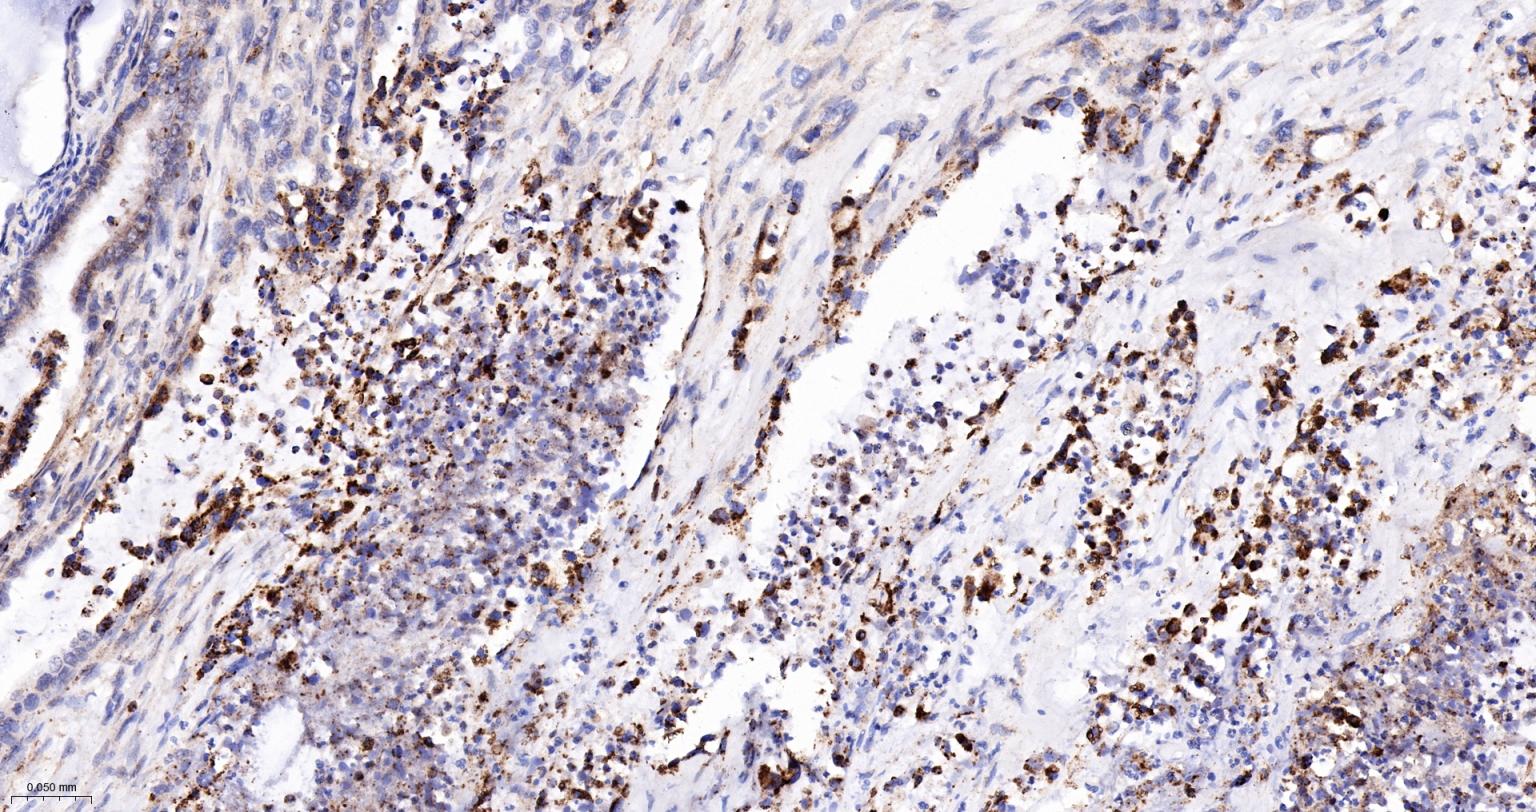

Paraformaldehyde-fixed, paraffin embedded Human Pancreatic Cancer; Antigen retrieval by boiling in sodium citrate buffer (pH6.0) for 15 min; The section was incubated with Midkine Monoclonal Antibody, Unconjugated (bsm-61219R) at 1:200 overnight at 4°C, followed by conjugation to the bs-0295G-HRP and DAB (C-0010) staining.

Paraformaldehyde-fixed, paraffin embedded Human Liver Cancer; Antigen retrieval by boiling in sodium citrate buffer (pH6.0) for 15 min; The section was incubated with Midkine Monoclonal Antibody, Unconjugated (bsm-61219R) at 1:200 overnight at 4°C, followed by conjugation to the bs-0295G-HRP and DAB (C-0010) staining.